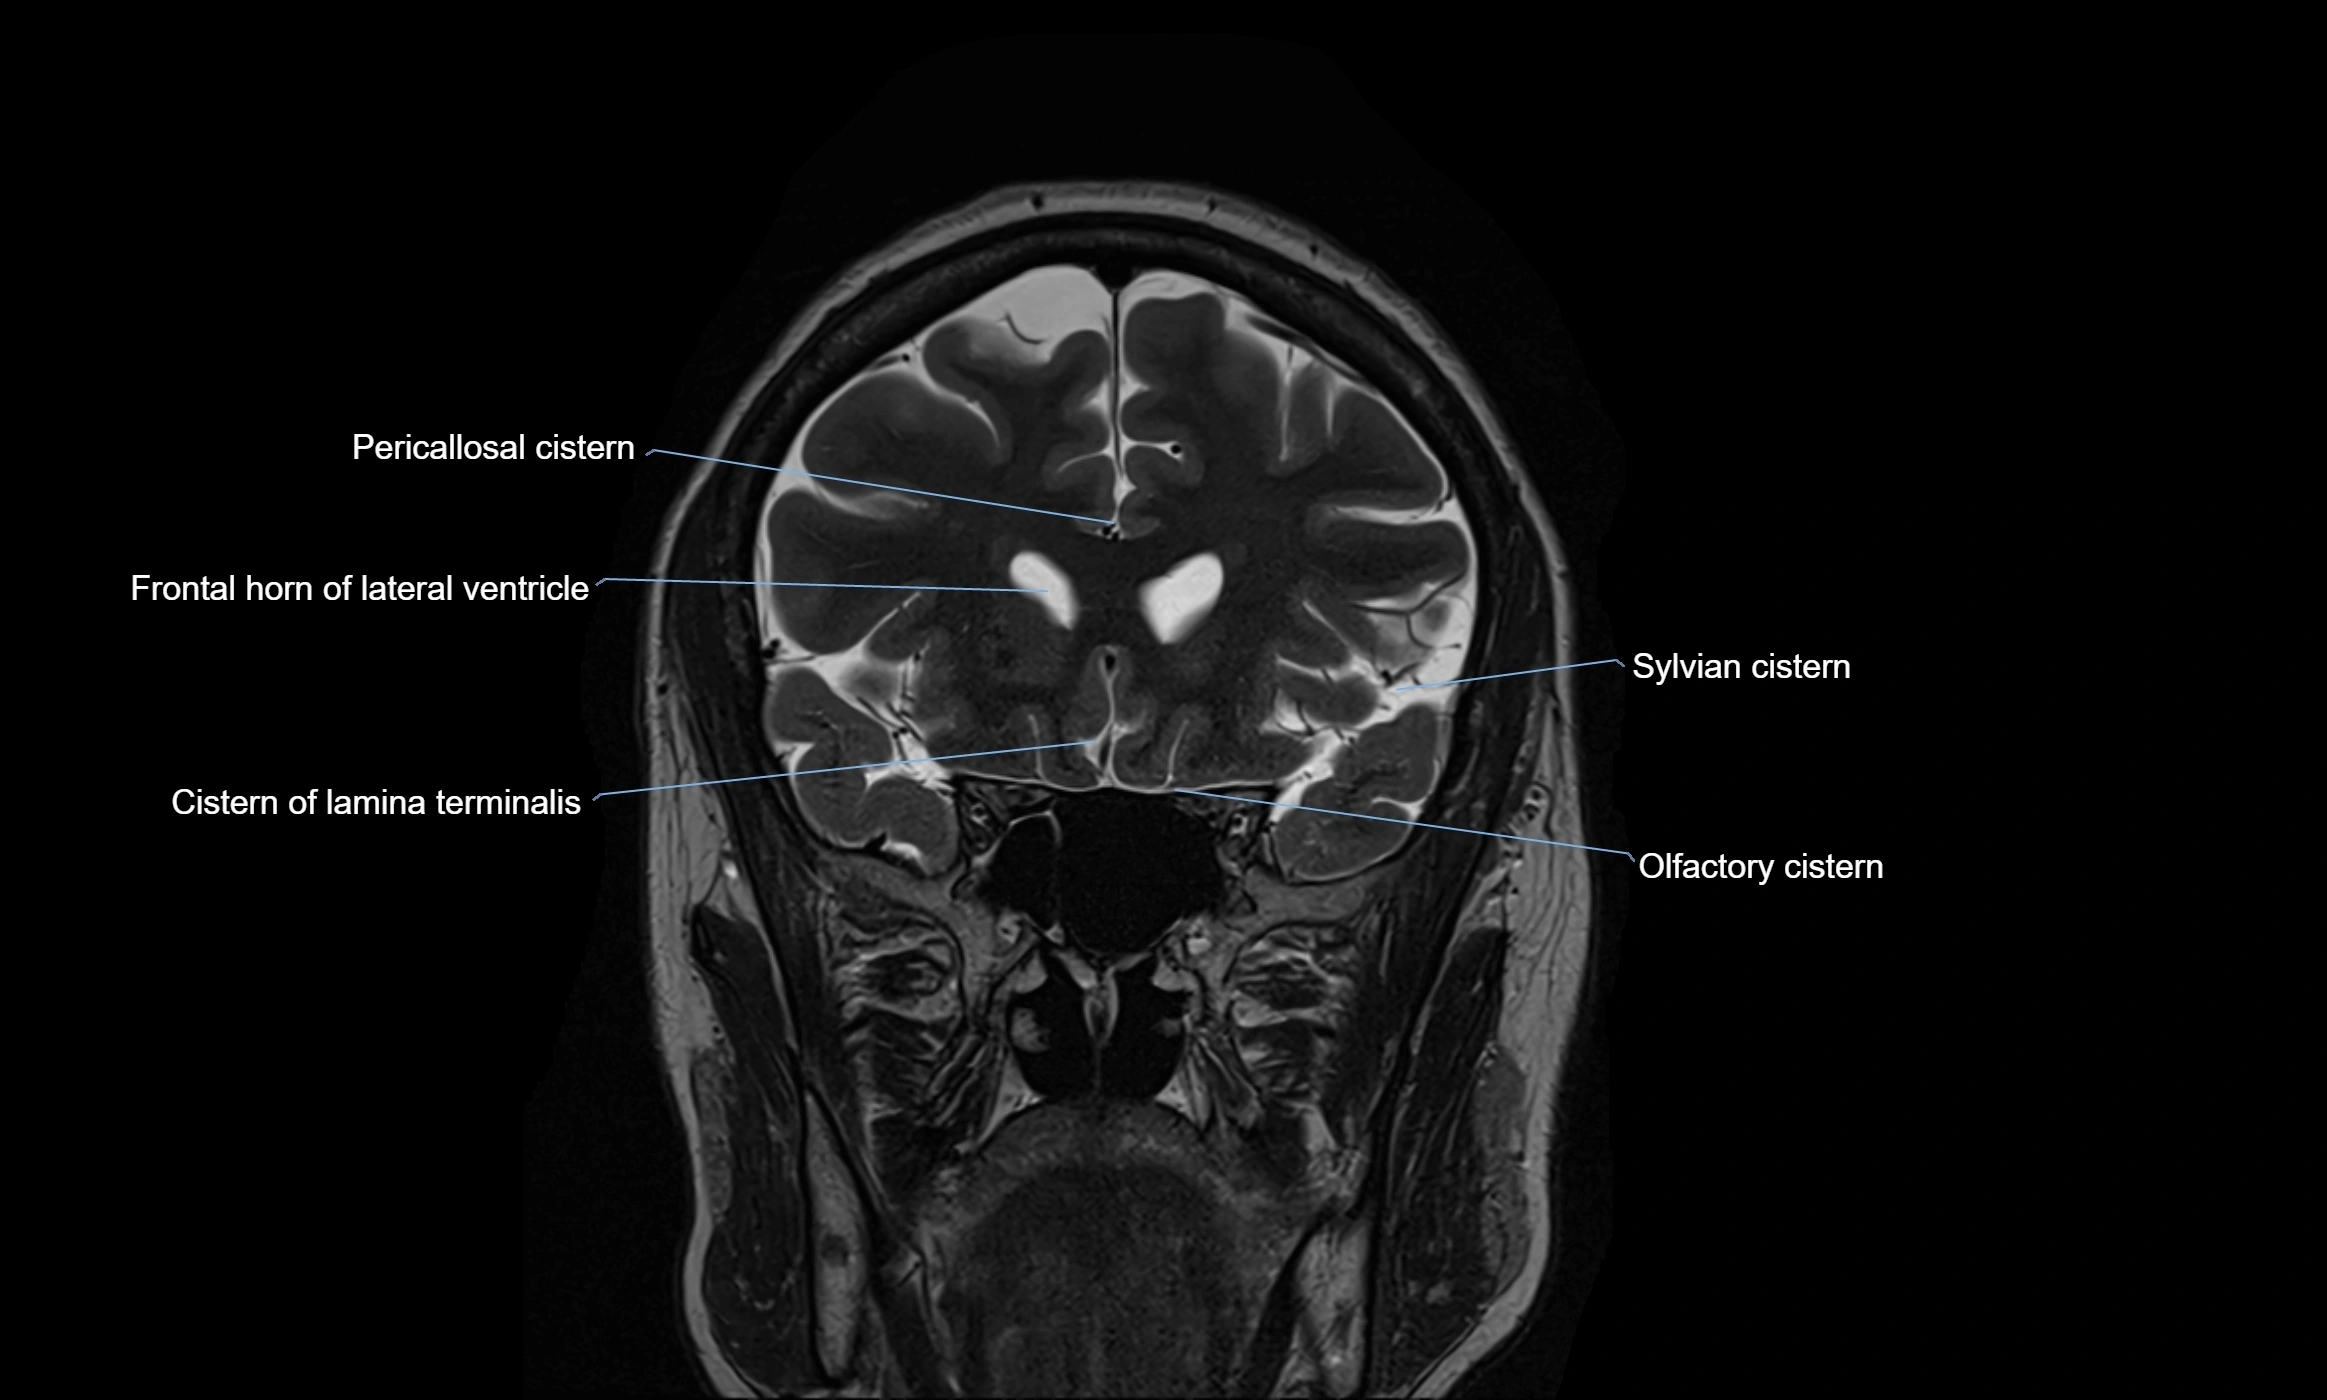

MRI images

image